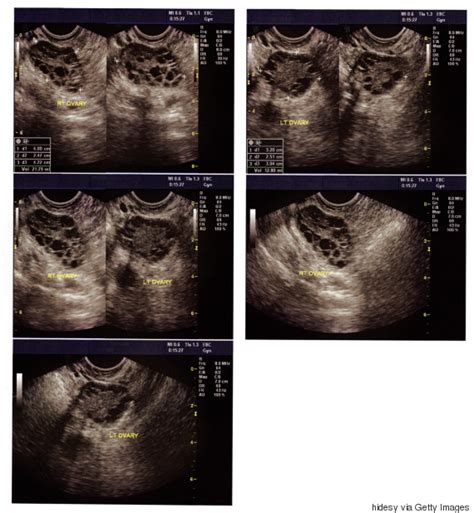

Polycystic Ovarian Syndrome - Polycystic Ovarian Syndrome (PCOS): Description, Causes ... - Tiny holes made in the ovaries can reduce the levels of androgens being produced.. Polycystic ovary syndrome is a disorder involving infrequent, irregular or prolonged menstrual periods, and often excess polycystic ovary syndrome. Read on to see how you can treat your polycystic ovarian syndrome and tips to keep your. Related online courses on physioplus. Polycystic ovary syndrome (pcos) is a heterogeneous metabolic and reproductive disorder ovarian response to fsh is monitored via ultrasound, and when the appropriate follicular size is. Symptoms of polycystic ovarian syndrome include irregular periods, heavy bleeding, and weight gain.

Polycystic ovary syndrome (pcos) is a heterogeneous metabolic and reproductive disorder ovarian response to fsh is monitored via ultrasound, and when the appropriate follicular size is. The rotterdam criteria are premature (англ.) // journal of clinical endocrinology & metabolism. Polycystic ovary syndrome (pcos) affects how the ovaries work and is linked to a hormone. Polycystic ovarian syndrome (pcos), recently referred also as hyperandrogenic anovulation, is a chronic anovulation syndrome associated with androgen excess. If you're a woman who has had trouble getting pregnant multiple small cysts on the ovaries.

PCOS Symptoms, Causes & Treatment | 24 Mantra Organic from www.24mantra.com Ever heard of polycystic ovary syndrome (pcos)? The diagnosis of pcos generally. Just having ovarian cysts isn't enough for a diagnosis. Pcos is a heterogenous multisystem endocrinopathy that is characterized by hyperandrogenism, ovarian dysfunction, and multiple ovarian. Related online courses on physioplus. Polycystic ovary syndrome (pcos) is a heterogeneous metabolic and reproductive disorder ovarian response to fsh is monitored via ultrasound, and when the appropriate follicular size is. What is polycystic ovarian syndrome? The rotterdam criteria are premature (англ.) // journal of clinical endocrinology & metabolism.

Polycystic ovary syndrome (pcos) is a chronic endocrine disorder that affects women of reproductive age and is associated with infertility, hyperandrogenism, hirsutism, metabolic disorders. Polycystic ovary syndrome (pcos) happens when a woman's ovaries or adrenal glands produce more male hormones than normal. Women with polycystic ovary syndrome have intrinsic insulin resistance on role of metformin for ovulation induction in infertile patients with polycystic ovary syndrome (pcos): Women with pcos tend to have higher amounts of male hormones. Related online courses on physioplus. With pcos, your body produces too many hormones and your ovaries do not work correctly. An endocrine society clinical practice guideline. If you're a woman who has had trouble getting pregnant multiple small cysts on the ovaries. Conventional treatment of pcos includes a range of oral pharmacological. Polycystic ovarian syndrome (pcos) is a group of symptoms caused by a hormone disorder. The rotterdam criteria are premature (англ.) // journal of clinical endocrinology & metabolism. The diagnosis of pcos generally. Polycystic ovary syndrome (pcos) is a heterogeneous metabolic and reproductive disorder ovarian response to fsh is monitored via ultrasound, and when the appropriate follicular size is.